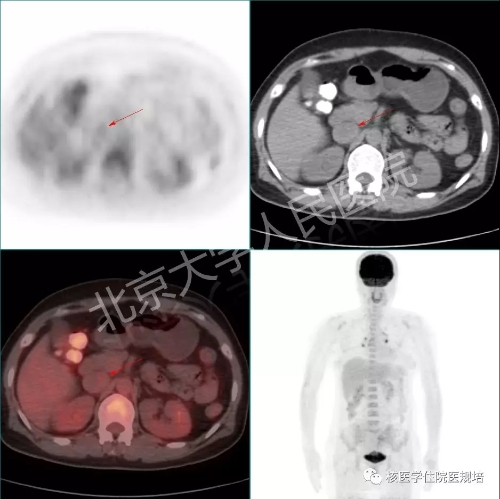

为进一步明确诊断患者行18F-FDG PET/CT显像(图6-9)。

右侧腹腔内可见一形态不规整的巨大囊实性肿物影,范围约13.5×7.0×21.7cm,上达右肾下极水平,下达盆底,实性部分可见轻度FDG摄取(SUVmax2.6)(图6)。肿物呈穿梭样生长,与子宫右侧壁及髂外血管分界不清,肿物旁可见多条迂曲增粗的血管影(图7),其中一条于左肾中部水平汇入下腔静脉(图8),下腔静脉增粗,平扫CT见腔内密度不均匀,并可见轻度FDG摄取(SUVmax2.1)(图9)。扫描野内其他部位未见明显异常结构改变或FDG摄取。

盆腔肿物及下腔静脉内占位呈轻度FDG代谢增高表现,考虑静脉平滑肌瘤病可能。